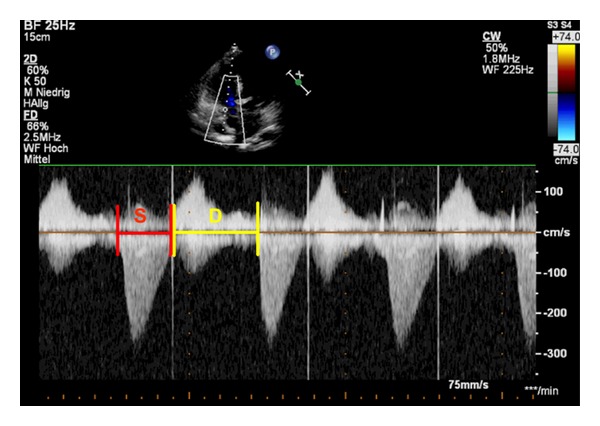

经胸超声心动图(TTE)是诊断和随访儿童和青壮年先天性心脏病(CHD)的一线工具。适当使用TTE可以减少对更多侵入性方式的需求,如心导管插入术和心脏磁共振成像。最近出现了新的超声心动图技术:组织多普勒成像,组织跟踪(应变和应变率),矢量速度成像(VVI),心肌性能指数,等容积加速(IVA)期间的心肌加速,收缩期与舒张期持续时间之比(S/D比),以及收缩期右心室(RV)功能的二维测量(如三尖瓣环平面收缩位移,TAPSE)。这些可能成为心室功能、顺应性和疾病进展的有价值的指标。此外,用于评估瓣膜功能、装置位置和心室容积的三维超声心动图正在被纳入常规临床护理。本文就这些超声心动图技术在冠心病患者中的潜在应用和局限性进行了讨论。特别关注的是超声心动图评估与右心室容量增加(如法洛四联症修复后的肺反流)或儿童和年轻人压力(如肺动脉高压)相关的右心室(RV)功能。

Transthoracic echocardiography (TTE) is the first-line tool for diagnosis and followup of pediatric and young adult patients with congenital heart disease (CHD). Appropriate use of TTE can reduce the need for more invasive modalities, such as cardiac catheterization and cardiac magnetic resonance imaging. New echocardiographic techniques have emerged more recently: tissue Doppler imaging, tissue tracking (strain and strain rate), vector velocity imaging (VVI), myocardial performance index, myocardial acceleration during isovolumic acceleration (IVA), the ratio of systolic to diastolic duration (S/D ratio), and two dimensional measurements of systolic right ventricular (RV) function (e.g., tricuspid annular plane systolic excursion, TAPSE). These may become valuable indicators of ventricular performance, compliance, and disease progression. In addition, three-dimensional (3D) echocardiography when performed for the assessment of valvular function, device position, and ventricular volumes is being integrated into routine clinical care. In this paper, the potential use and limitations of these new echocardiographic techniques in patients with CHD are discussed. A particular focus is on the echocardiographic assessment of right ventricular (RV) function in conditions associated with increased right ventricular volume (e.g., pulmonary regurgitation after tetralogy of Fallot repair) or pressure (e.g., pulmonary hypertension) in children and young adults.